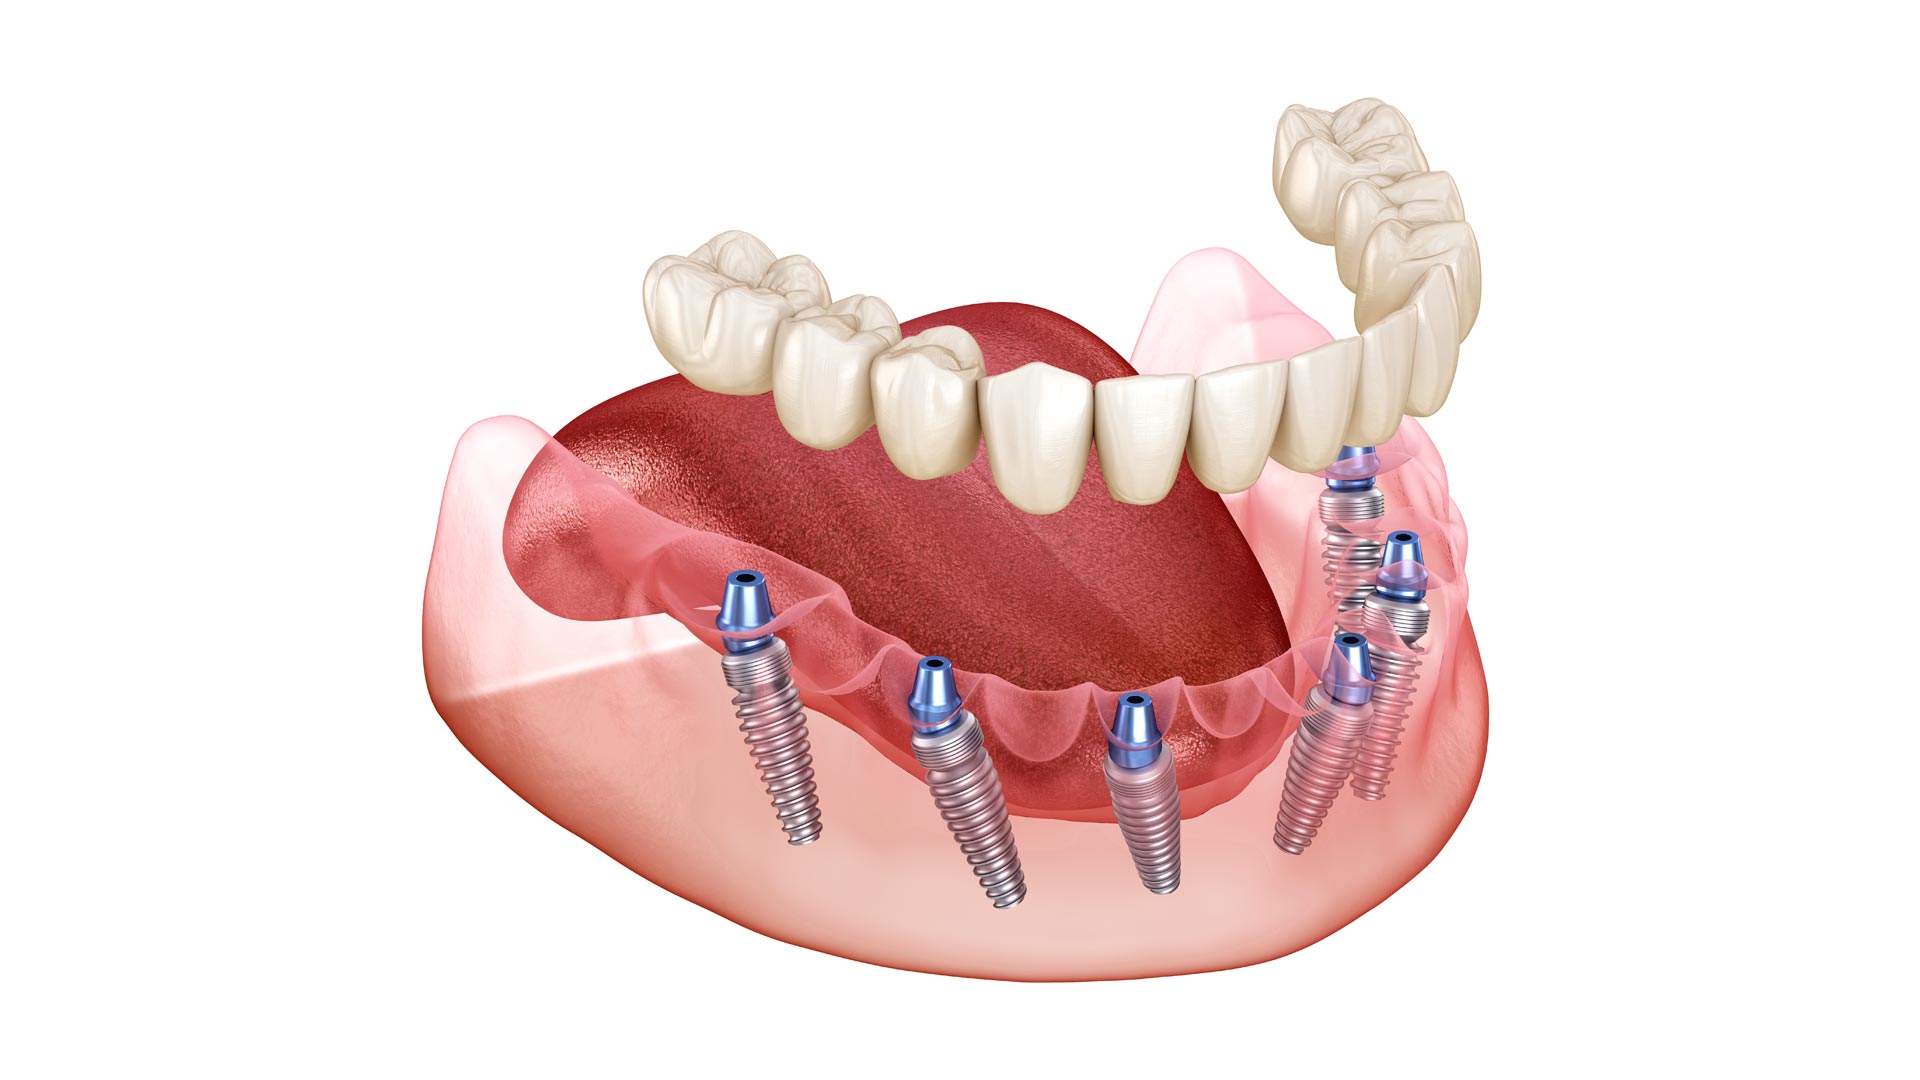

Пошаговое руководство по установке съёмного протеза на импланты